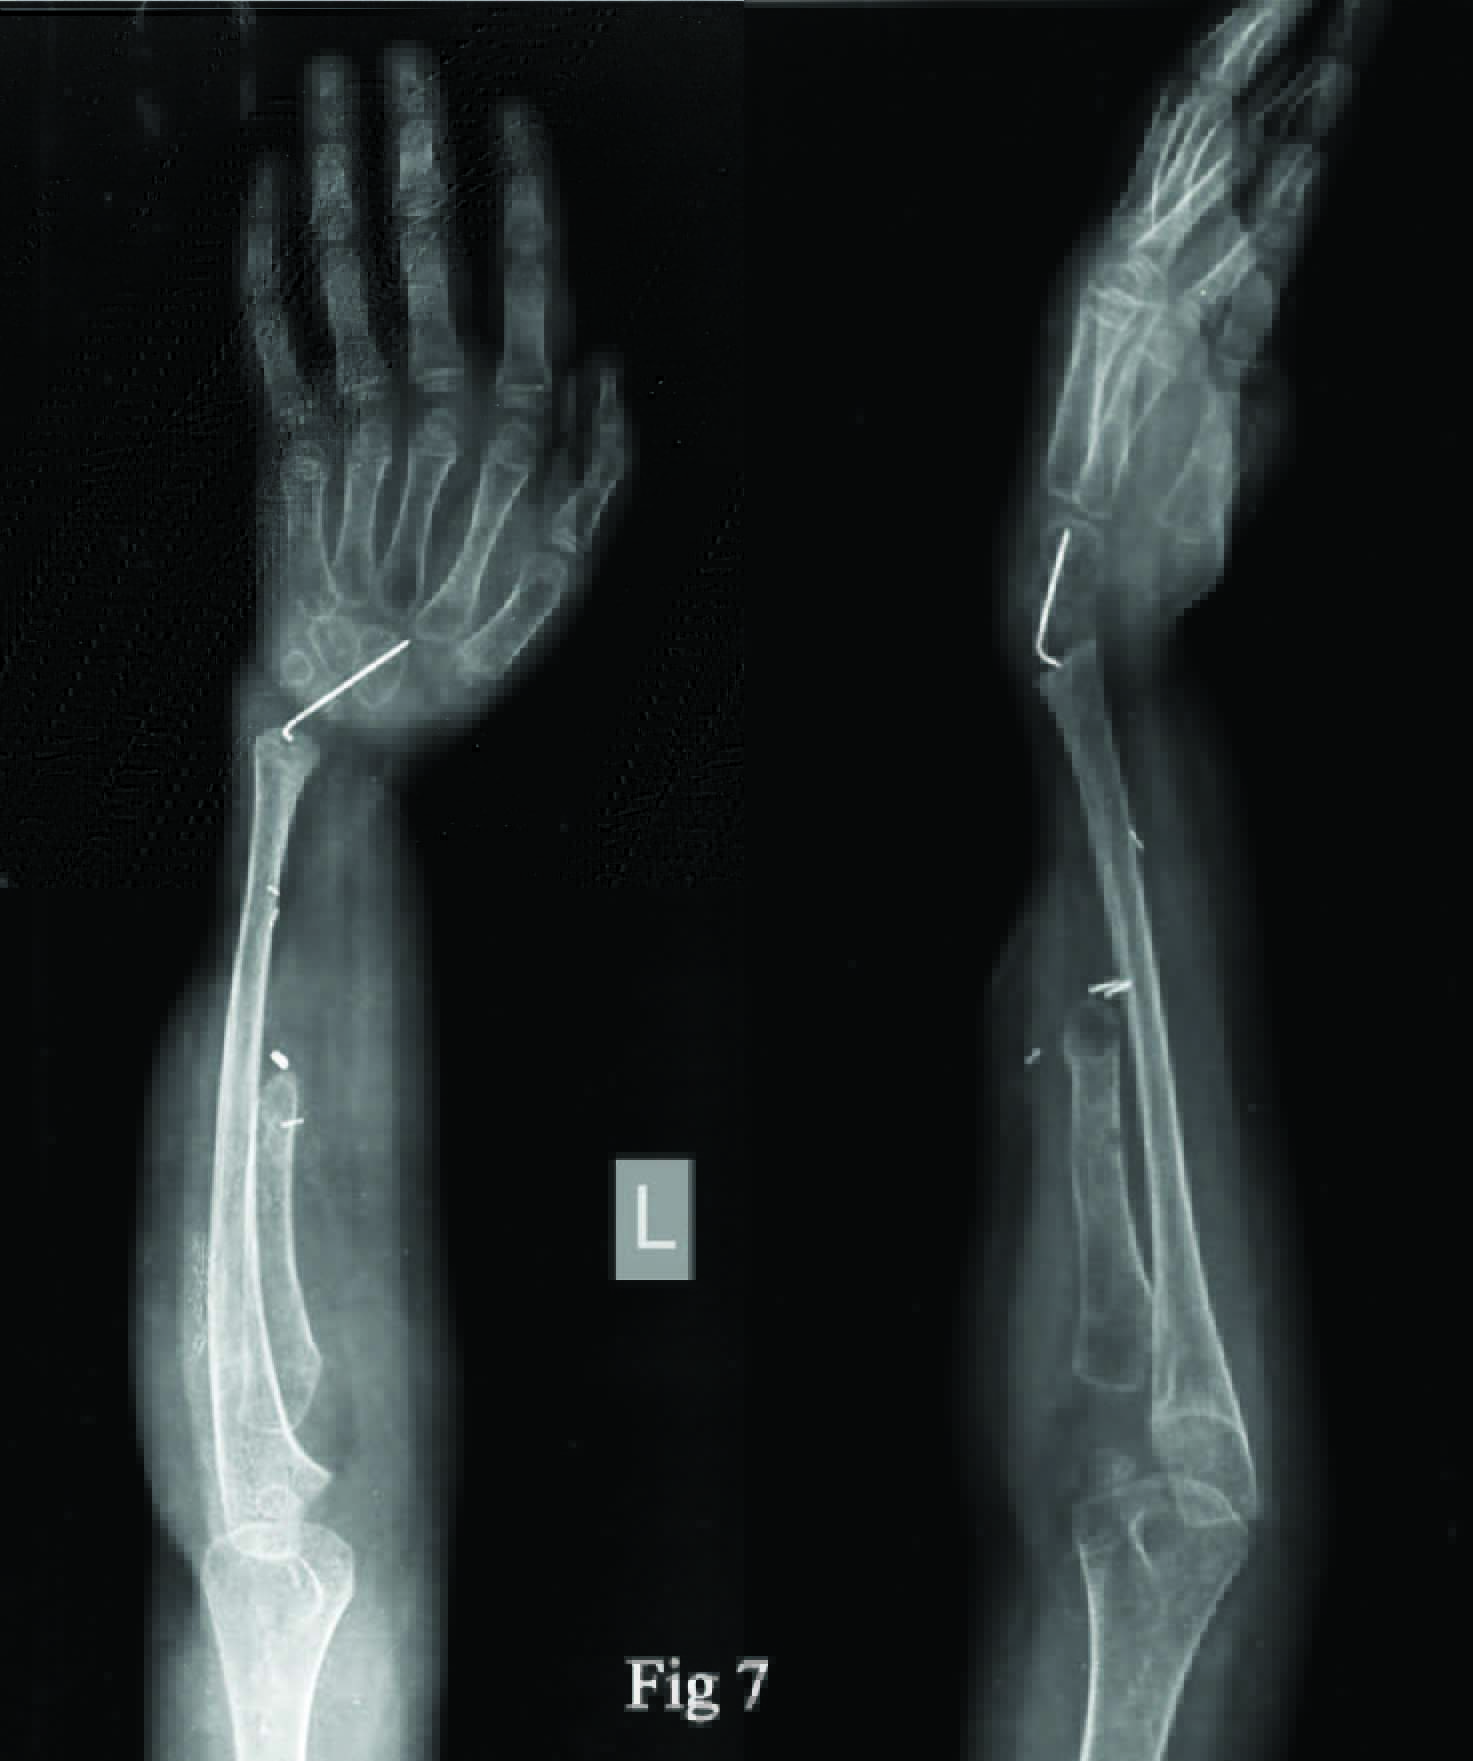

Seven centimeter from articular surface a radial osteotomy was done and specimen delivered [Table/Fig-5]. The carpus was centralized over ulna. Considering the age of the patient it was decided to stabilize the ulnocarpal interface using unthreaded K wires passed through the distal ulna including the distal ulnar physis with a plan to go for ulnocarpal arthrodesis as a definitive procedure at skeletal maturity. Postoperatively the wrist was immobilized in a POP cast for six weeks [Table/Fig-6]. This was followed by a forearm brace immobilization to be continued till skeletal maturity [Table/Fig-7&8]. Supervised regular physiotherapy was recommended to reduce the chance of reflex sympathetic dystrophy.

Postop X-rays showing centralisation of carpus on ulna and ulnocarpal stabilization(solid arrow) with resected radius (arrow)